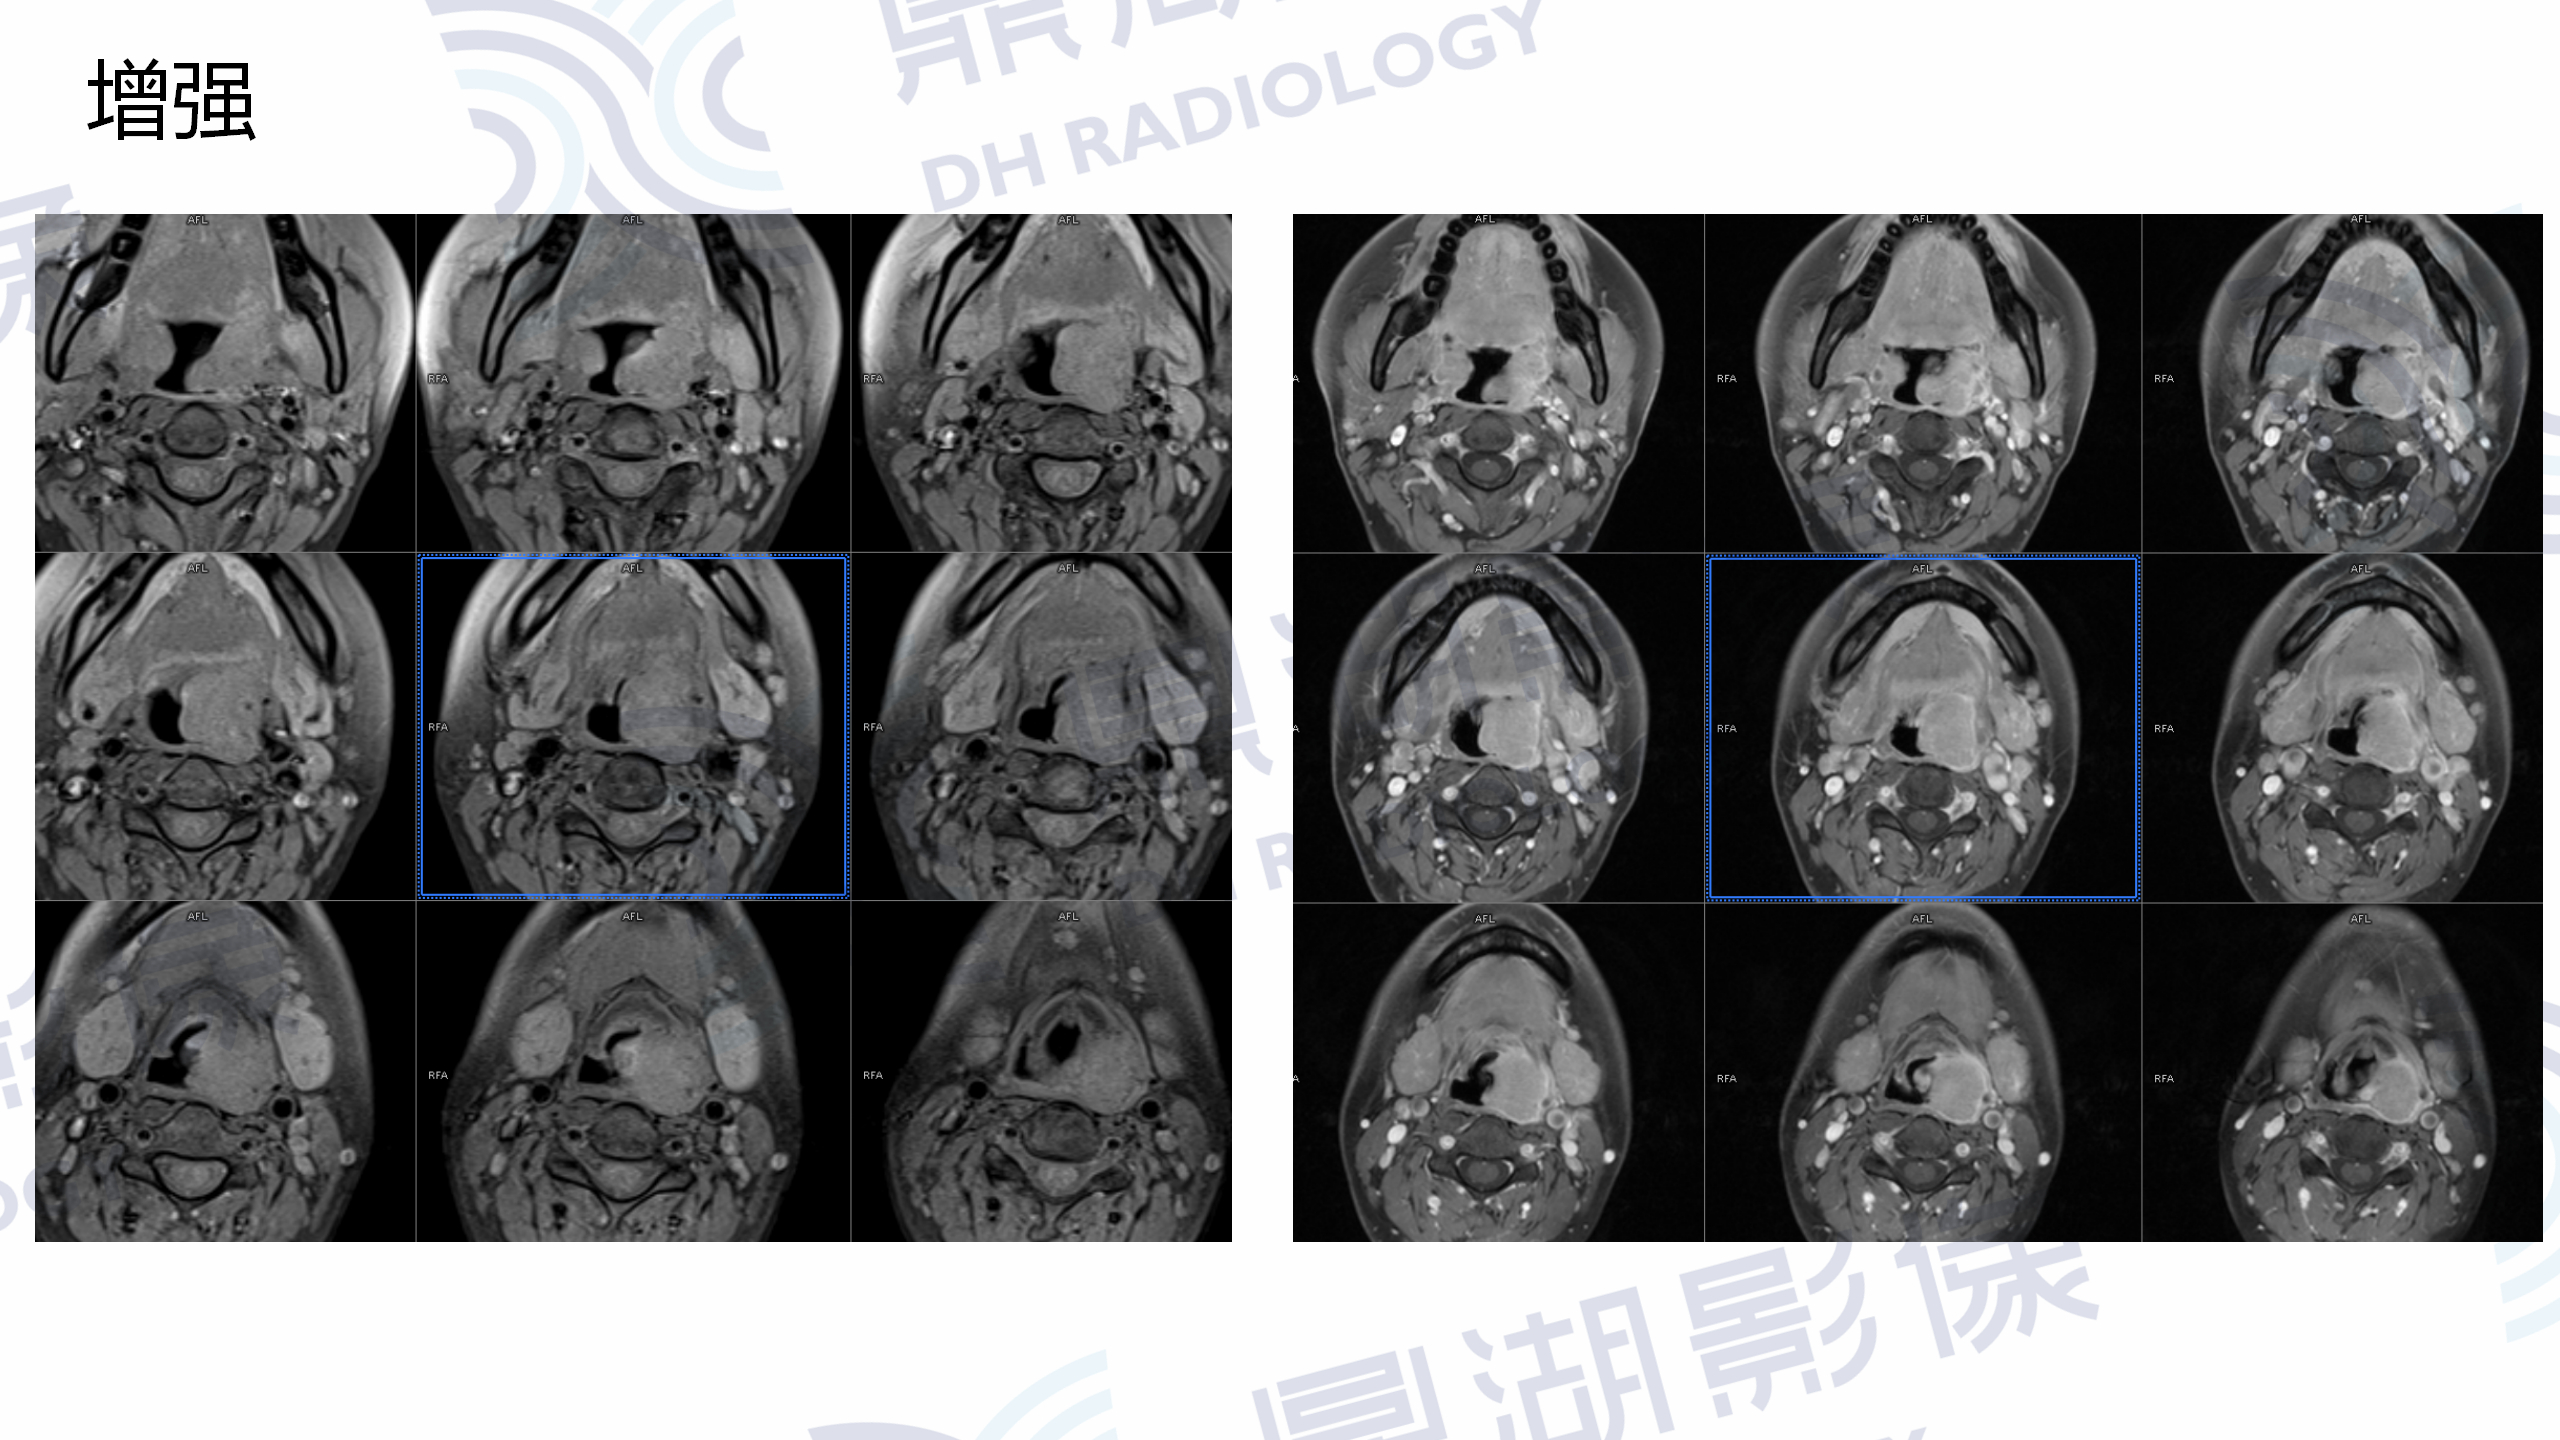

MR增强检查提示:口咽左侧壁至左侧声门上不规则软组织肿块,病灶突入咽腔,信号均匀,T1WI呈等信号,T2W呈稍高信号,DWI呈高信号,增强扫描呈轻度均匀强化,左侧杓状会厌皱襞水肿,左侧梨状窝消失。